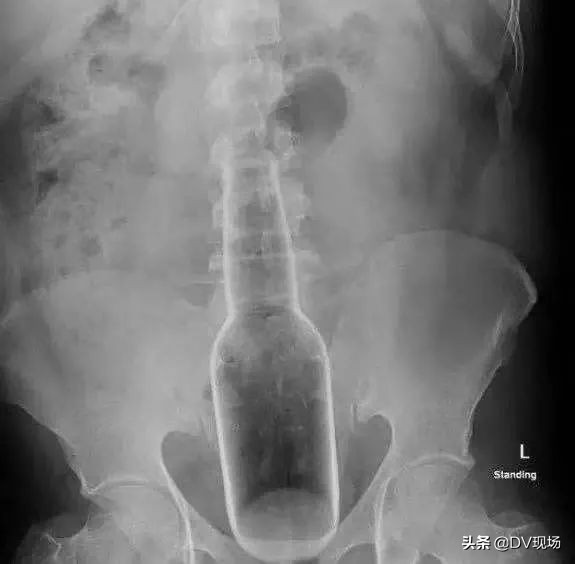

经过仔细检查

眼前的一幕可把医生吓坏了

大叔的直肠里

竟然出现了一个 瓶状物 !

这么大一个块头

最终

医生为大叔进行“直肠异物取出术”

藏在体内的瓶子

终于再一次重见天日!

就是这个!

长18cm、直径5cm的瓶子!